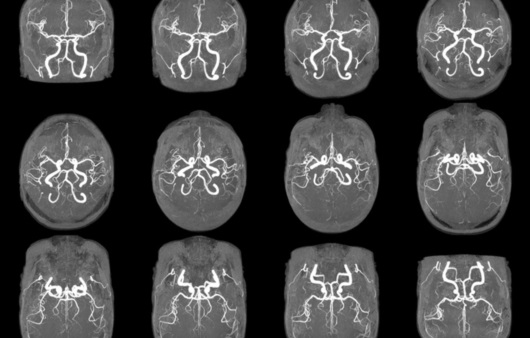

반면에 MRA(자기 공명 혈관 영상)는 MRI의 일종으로, 혈관의 이미지를 생성하는 데 초점을 맞추고 있습니다. 이는 혈관의 구조 및 흐름을 평가하는 데 유용하며, 주로 심혈관 질환의 진단에 사용됩니다. MRA는 특히 혈관의 협착이나 막힘, 동맥류와 같은 혈관 관련 문제를 발견하는 데 매우 유용합니다.

MRA는 MRI의 기법을 기반으로 하므로, 기본적으로는 동일한 작동 원리를 가지고 있지만, 약간의 차이점이 있습니다. MRA는 특히 혈관을 시각화하는 데 최적화되어 있으며, 주로 조영제를 사용하여 혈관을 더욱 뚜렷하게 구분합니다. 조영제는 혈관 내에서 신호의 차이를 만들어 신호 강도를 높여줍니다. 이로 인해 혈관의 형태와 상태를 더욱 명확하게 시각화할 수 있습니다.

- 혈관 질환의 조기 발견에 특화되어 있다.

- 비침습적인 방법으로 혈관 상태를 평가할 수 있다.

MRA는 다음과 같은 상황에서 자주 사용됩니다.

- 동맥류 및 혈관 협착의 평가

- 심혈관 질환 위험 환자의 혈관 상태 진단

- 선천적 심장 질환 및 혈관 기형의 확인